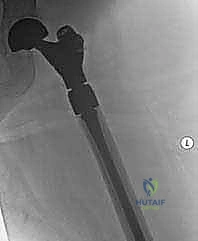

- اختيار نوع المفصل الاصطناعي: بناءً على صور الأشعة المقطعية، يحدد الجراح نوع المفصل. في حالات الأورام، غالباً ما تُستخدم مفاصل ذات جذوع طويلة (Long-stem prostheses) لتجاوز منطقة الورم وتثبيت المفصل في العظم السليم أسفل الآفة. كما تُستخدم تقنية الأسمنت العظمي (Bone Cement - PMMA) بكثافة لتوفير استقرار فوري للمفصل والسماح للمريض بالمشي في اليوم التالي.

الخطوة 4: تحضير عظم الفخذ وتثبيت الجذع (Femoral Stem Insertion)

- يتم تجويف القناة النخاعية داخل عظم الفخذ لتتناسب مع حجم الجذع المعدني (Stem).

- في مرضى السرطان النقيلي، يُفضل استخدام الأسمنت العظمي لتثبيت الجذع. الأسمنت العظمي لا يعمل كصمغ فقط، بل كحشوة تملأ الفراغات التي تركها الورم وتوفر دعماً ميكانيكياً فورياً.

- يتم وضع رأس معدني أو خزفي (Ceramic Head) على قمة الجذع.